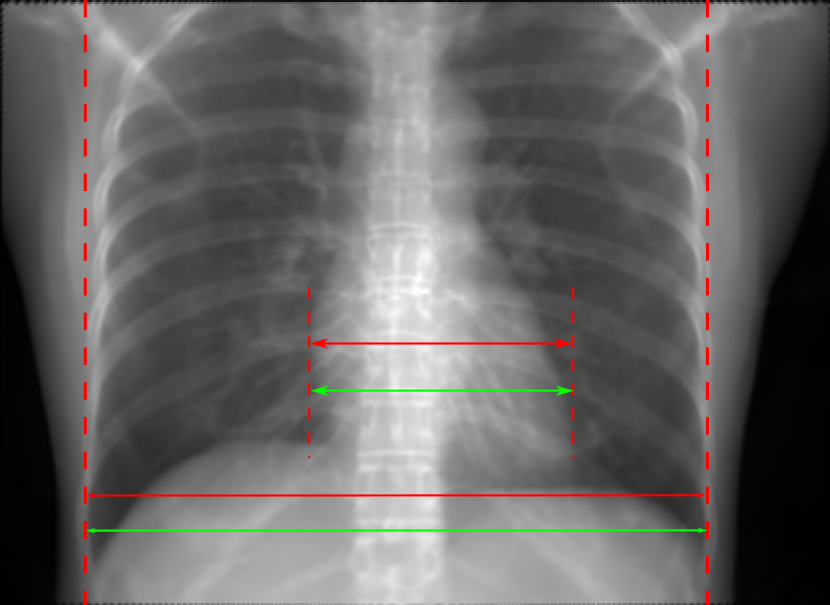

Figure 10: Perspective deformation learning in one exemplary patient case for chest X-ray imaging. The maximal horizontal cardiac diameter and the maximal horizontal thoracic diameter in (b) and (d)-(f) are indicated by the horizontal red lines, while those in the reference image (a) are green lines. The cardiothoracic ratio, RMSE, and SSIM for each image is displayed in its corresponding subcaption.

The results of one patient in chest X-ray imaging are displayed in Fig. 10, where the cardiothoracic ratio is assessed as an exemplary clinical application [32]. In the reference image (Fig. 10(a)), the maximal horizontal cardiac diameter (MHCD) and the maximal horizontal thoracic diameter (MHTD) are indicated by two green horizontal lines. Its cardiothoracic ratio is 0.4237. In the 0superscript00^{\circ} perspective projection image (Fig. 10(b)), all the anatomical structures can be visualized with fine resolution. However, due to perspective deformation, anatomical structures, e.g. the ribs and the spine, are deformed. The deformations are visualized better in the difference image Fig. 10(c). Compared with the ribs and the spine, the heart has less deformation as its location is closer to the isocenter. In Fig. 10(b), the MHCD and the MHTD are indicated by two red horizontal lines, while the green lines are those of the reference image. While the MHCD has changed little from 10.47 cm to 10.16 cm, the MHTD has changed considerably from 24.71 cm to 25.40 cm. As a consequence, the cardiothoracic ratio becomes 0.4002, which is below the normal range of 0.42 - 0.50 [32]. The result of learning perspective deformation from 0superscript00^{\circ} single view is displayed in Fig. 10(d), where the MHCD and the MHTD are 10.63 cm and 24.71 cm, respectively. The MHTD of Fig. 10(d) is the same as that of the reference image. This is also reflected by the difference image Fig. 10(g), where the lower ribs have small errors. However, the upper ribs as well as the spine still have considerable errors. The results of perspective deformation learning from 0&180superscript0superscript1800^{\circ}\&180^{\circ} views in Cartesian and polar coordinates are displayed in Fig. 10(e) and Fig. 10(f), respectively. The measured MHCDs and MHTDs in these two images are very close to the reference ones. Hence, their cardiothoracic ratios, 0.4214 and 0.4240 respectively, are close to the reference ratio as well. In the difference images (Fig. 10(h) and Fig. 10(i)), the errors of ribs and spine decrease as their boundaries are no longer apparently visible. Nevertheless, Fig. 10(i) has less error than Fig. 10(h), achieving the smallest RMSE value of 3.83. The quantitative evaluation of all the 162 testing datasets is displayed in Tab. II, where learning perspective deformation from two complementary views in polar coordinates achieves the least RMSE 4.98 and highest SSIM 0.9517, demonstrating the superiority of learning perspective deformation from two complementary views in polar coordinates.

The TransU-Net results are displayed in Figs. 10(j)-(l). Compared with their corresponding Pix2pixGAN results, the TransU-Net prediction images are more blurry, although the same perceptual loss is used. The error images in Figs. 10(m)-(o) indicate that TransU-Net reduces perspective deformation better with complementary views than a single view. The quantitative evaluation in Tab. II shows that TransU-Net cannot effectively reduce perspective deformation with a single view. With complementary views in both Cartesian and polar coordinate systems, TransU-Net achieves comparable performance, which is still considerably worse than that of Pix2pixGAN. The inferior performance of TransU-Net to Pix2pixGAN on the chest data is potentially caused by the repetitive nature of the segmental rib anatomy, which leads TransU-Net to be ineffective in extracting position-dependent features.